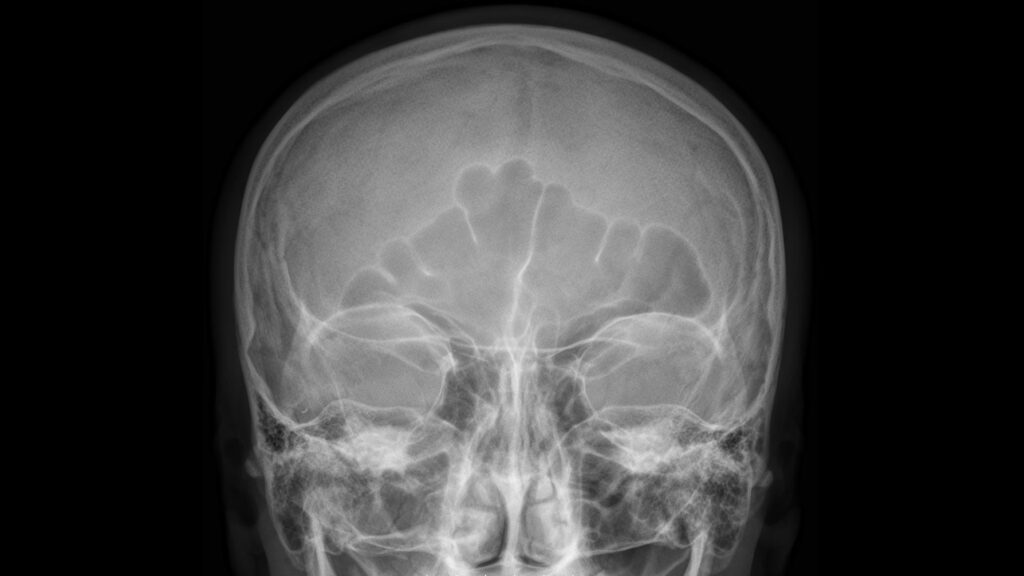

Un hombre de mediana edad acudió a un hospital para tratar unos fuertes dolores de cabeza. Cuando le hicieron una tomografía del cerebro, los médicos descubrieron un globo lleno de marihuana en su fosa nasal derecha. Según un informe del caso, el paciente había escondido la marihuana para pasarla como contrabando en la cárcel. Al…